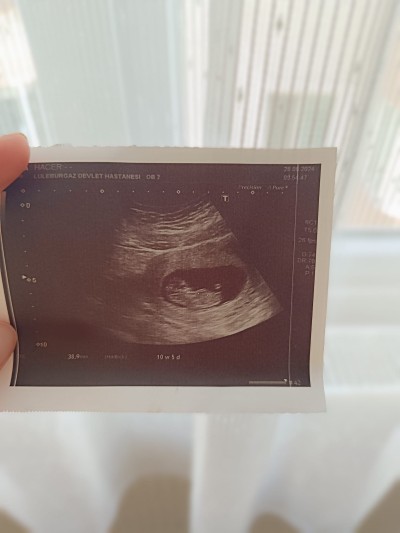

Cinsiyet tahmini alabilir miyim doktorum 16 haftalığa kadar yuzde doksan erkek dedi fakat 20 haftalık kontrolün de cinsiyet belli değil dedi ne erkege ne kiza benzetti değişebilir mi gerçekten

Gebelik haftası Şuan 20